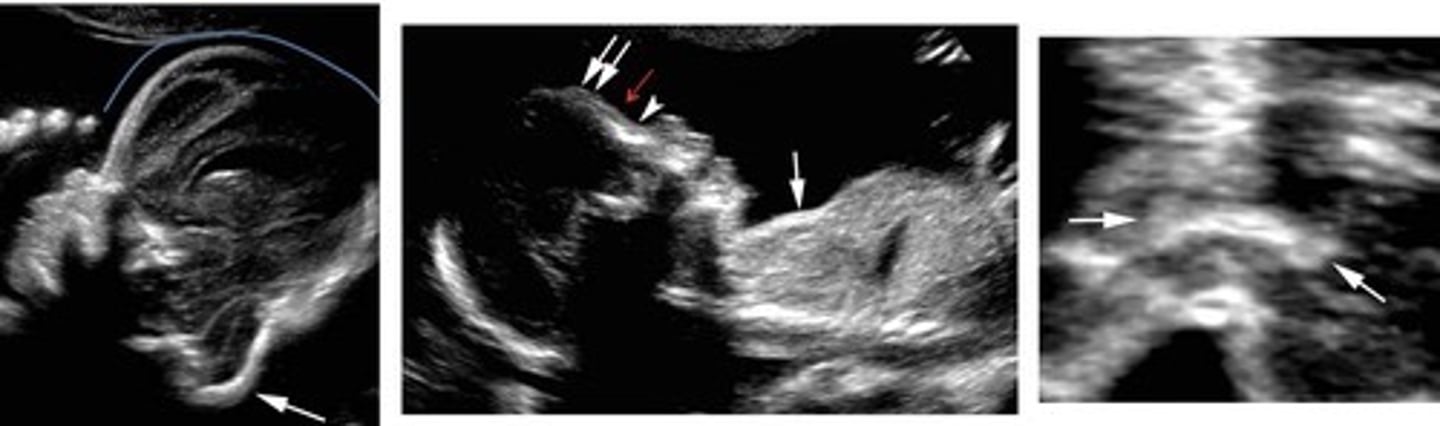

Spina Bifida

Spinal cord and/or vertebral column do not close properly

Associated with... Lemon-shaped head & Banana-shaped cerebellum

Spina Bifida Occulta

Cleft covered only by skin

Meningomyelocele

Meninges and neural elements herniate